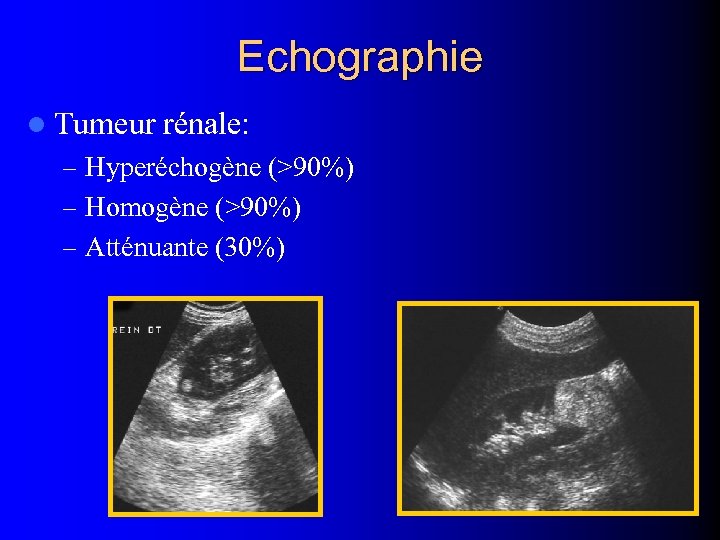

Echographie l Tumeur rénale: – Hyperéchogène (>90%) – Homogène (>90%) – Atténuante (30%)

Echographie l Tumeur rénale: – Hyperéchogène (>90%) – Homogène (>90%) – Atténuante (30%)